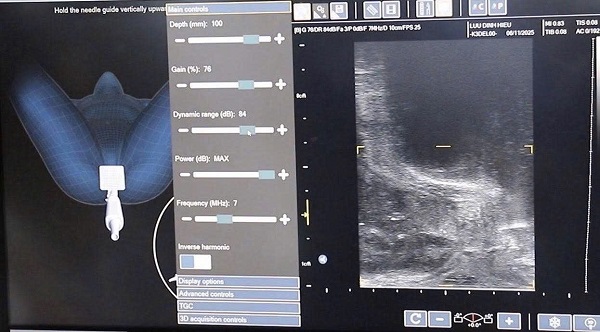

Điểm mấu chốt của “sinh thiết đích” là lấy đúng, đủ mô bệnh cần khảo sát. Ở trường hợp người bệnh này, bác sĩ sử dụng phối hợp các phương tiện hiện đại như: Chụp cộng hưởng từ MRI giúp xác định vùng tổn thương có đặc điểm ác tính rõ ràng; siêu âm đầu dò trực tràng hỗ trợ hướng dẫn can thiệp và lấy mẫu chính xác, tiện lợi. Nhờ các kĩ thuật hình ảnh chính xác, bác sĩ nhanh chóng xác định được vùng nghi ngờ tổn thương đích, ngay cả với những vùng khó tiếp cận, thực hiện sinh thiết đúng trọng tâm. Khi mẫu mô được lấy đúng, kết quả giải phẫu bệnh thường chính xác hơn, đồng thời giúp giảm thời gian chờ đợi cho chẩn đoán cuối cùng.